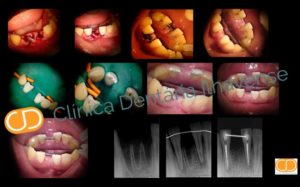

Avulsão Dentária Traumática

Como consequência de um acidente de carro ou trauma durante jogos e desporto, um dente intacto pode literalmente sofrer um traumatismo e sair do seu lugar natural, o alvéolo. A intervenção rápida e precisa permite que este dente seja reimplantado.

Tratamento Clínico efetuado por Dr. Pedro Galante na Clínica Dentária Ilhavense no âmbito do mestrado de Endodontia da Universitat Internacional de Catalunya.

– Barcelona 2008.